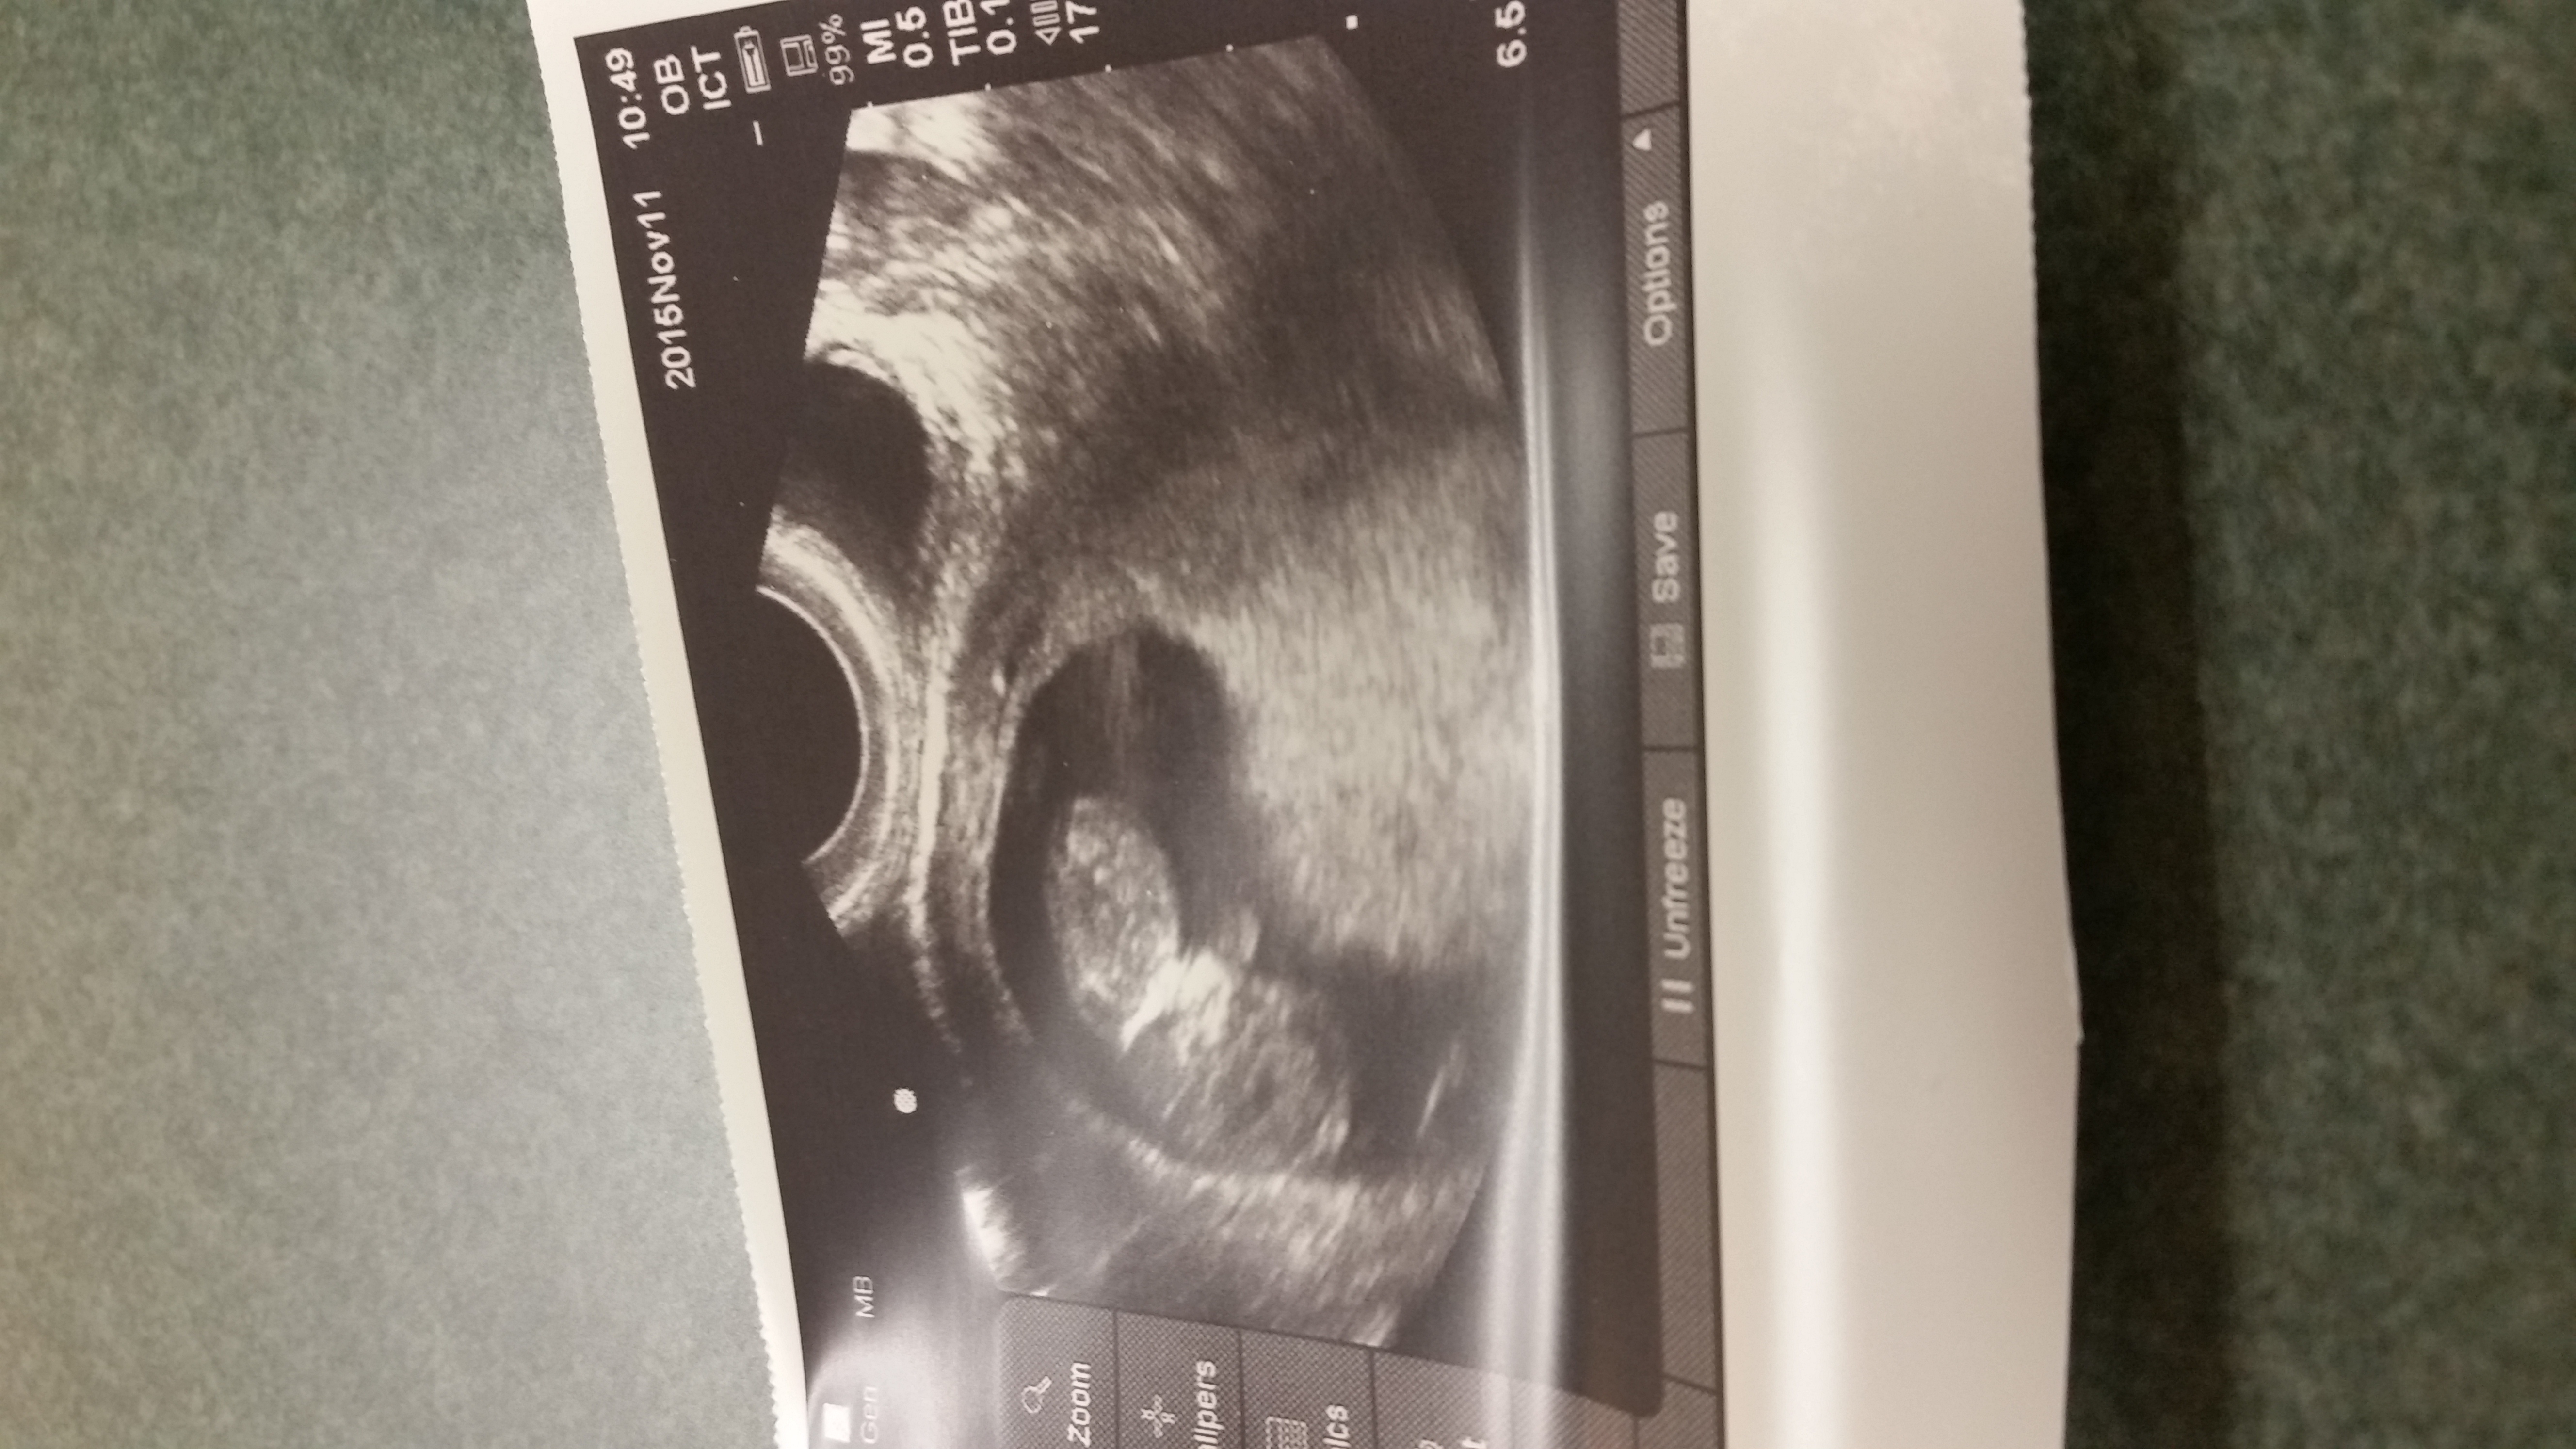

Here is our LO from our dating u/s yesterday (measuring 6w6d then, 7w today). It was so amazing & surreal to see its heart beating. I now fully understand "love at first sight." (So corny, I know lol)